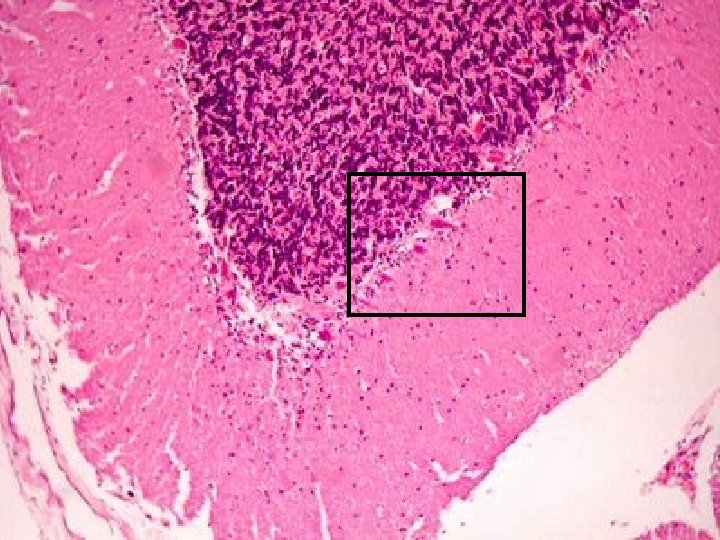

Capa de las células de Purkinje Célula de Purkinje Fibra trepadora Inhibición Célula nuclear profunda Excitación Aferencia (oliva inferior) Eferencia Capa Granulosa Células Granulares Núcleos profundos Fibra Musgosa Aferencias (El resto de aferentes) Corteza Capa Molecular

• El Cerebelo emite señales de encendido-apagado y Capa apagado-encendido Célula de Purkinje - Fibra trepadora Célula nuclear profunda Capa de las células de Purkinje Inhibición + Excitación + Aferencia (oliva inferior) Eferencia Capa Granulosa Células Granulares Núcleos profundos Fibra Musgosa Aferencias (El resto de aferentes) Corteza Molecular